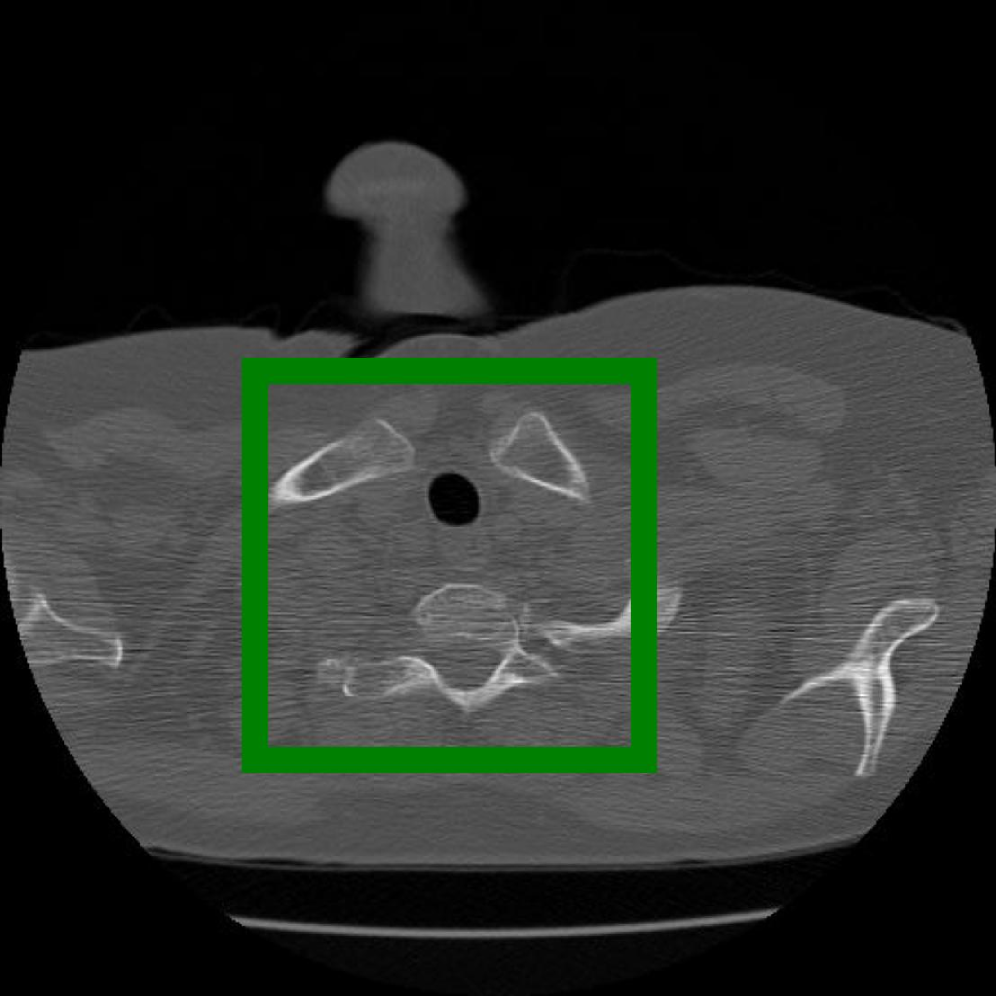

Figure 10: The visual comparison of different compression methods on a CT Heart Segmentation image.

Figure 11: Zoomed-in view of the highlighted region in Figure 10.

IV-B3 Visual Comparison

Figures 7 and 8 present representative examples from the CIL dataset and their zoomed-in regions, respectively. For the CT Heart Segmentation dataset, Figures 10 and 12 illustrate typical reconstruction results, while Figures 11 and 13 further enlarge local regions to compare structural details. Across both datasets, COLI preserves fine structures and global continuity well even at relatively low bpp. Specifically, on the CIL dataset, COLI attains the lowest bitrate among INR-based methods while still maintaining clear texture details. On the CT Heart dataset, COLI also operates at a low bpp within the INR family and delivers superior visual quality with improved detail fidelity and smoother structural presentation. The zoomed-in regions show fewer blocking artifacts and smoother transitions, making COLI especially suitable for large images and medical images. These visual results validate that INR-based compression can achieve efficient storage with reliable perceptual consistency, offering practical advantages for real-world large-scale image processing.